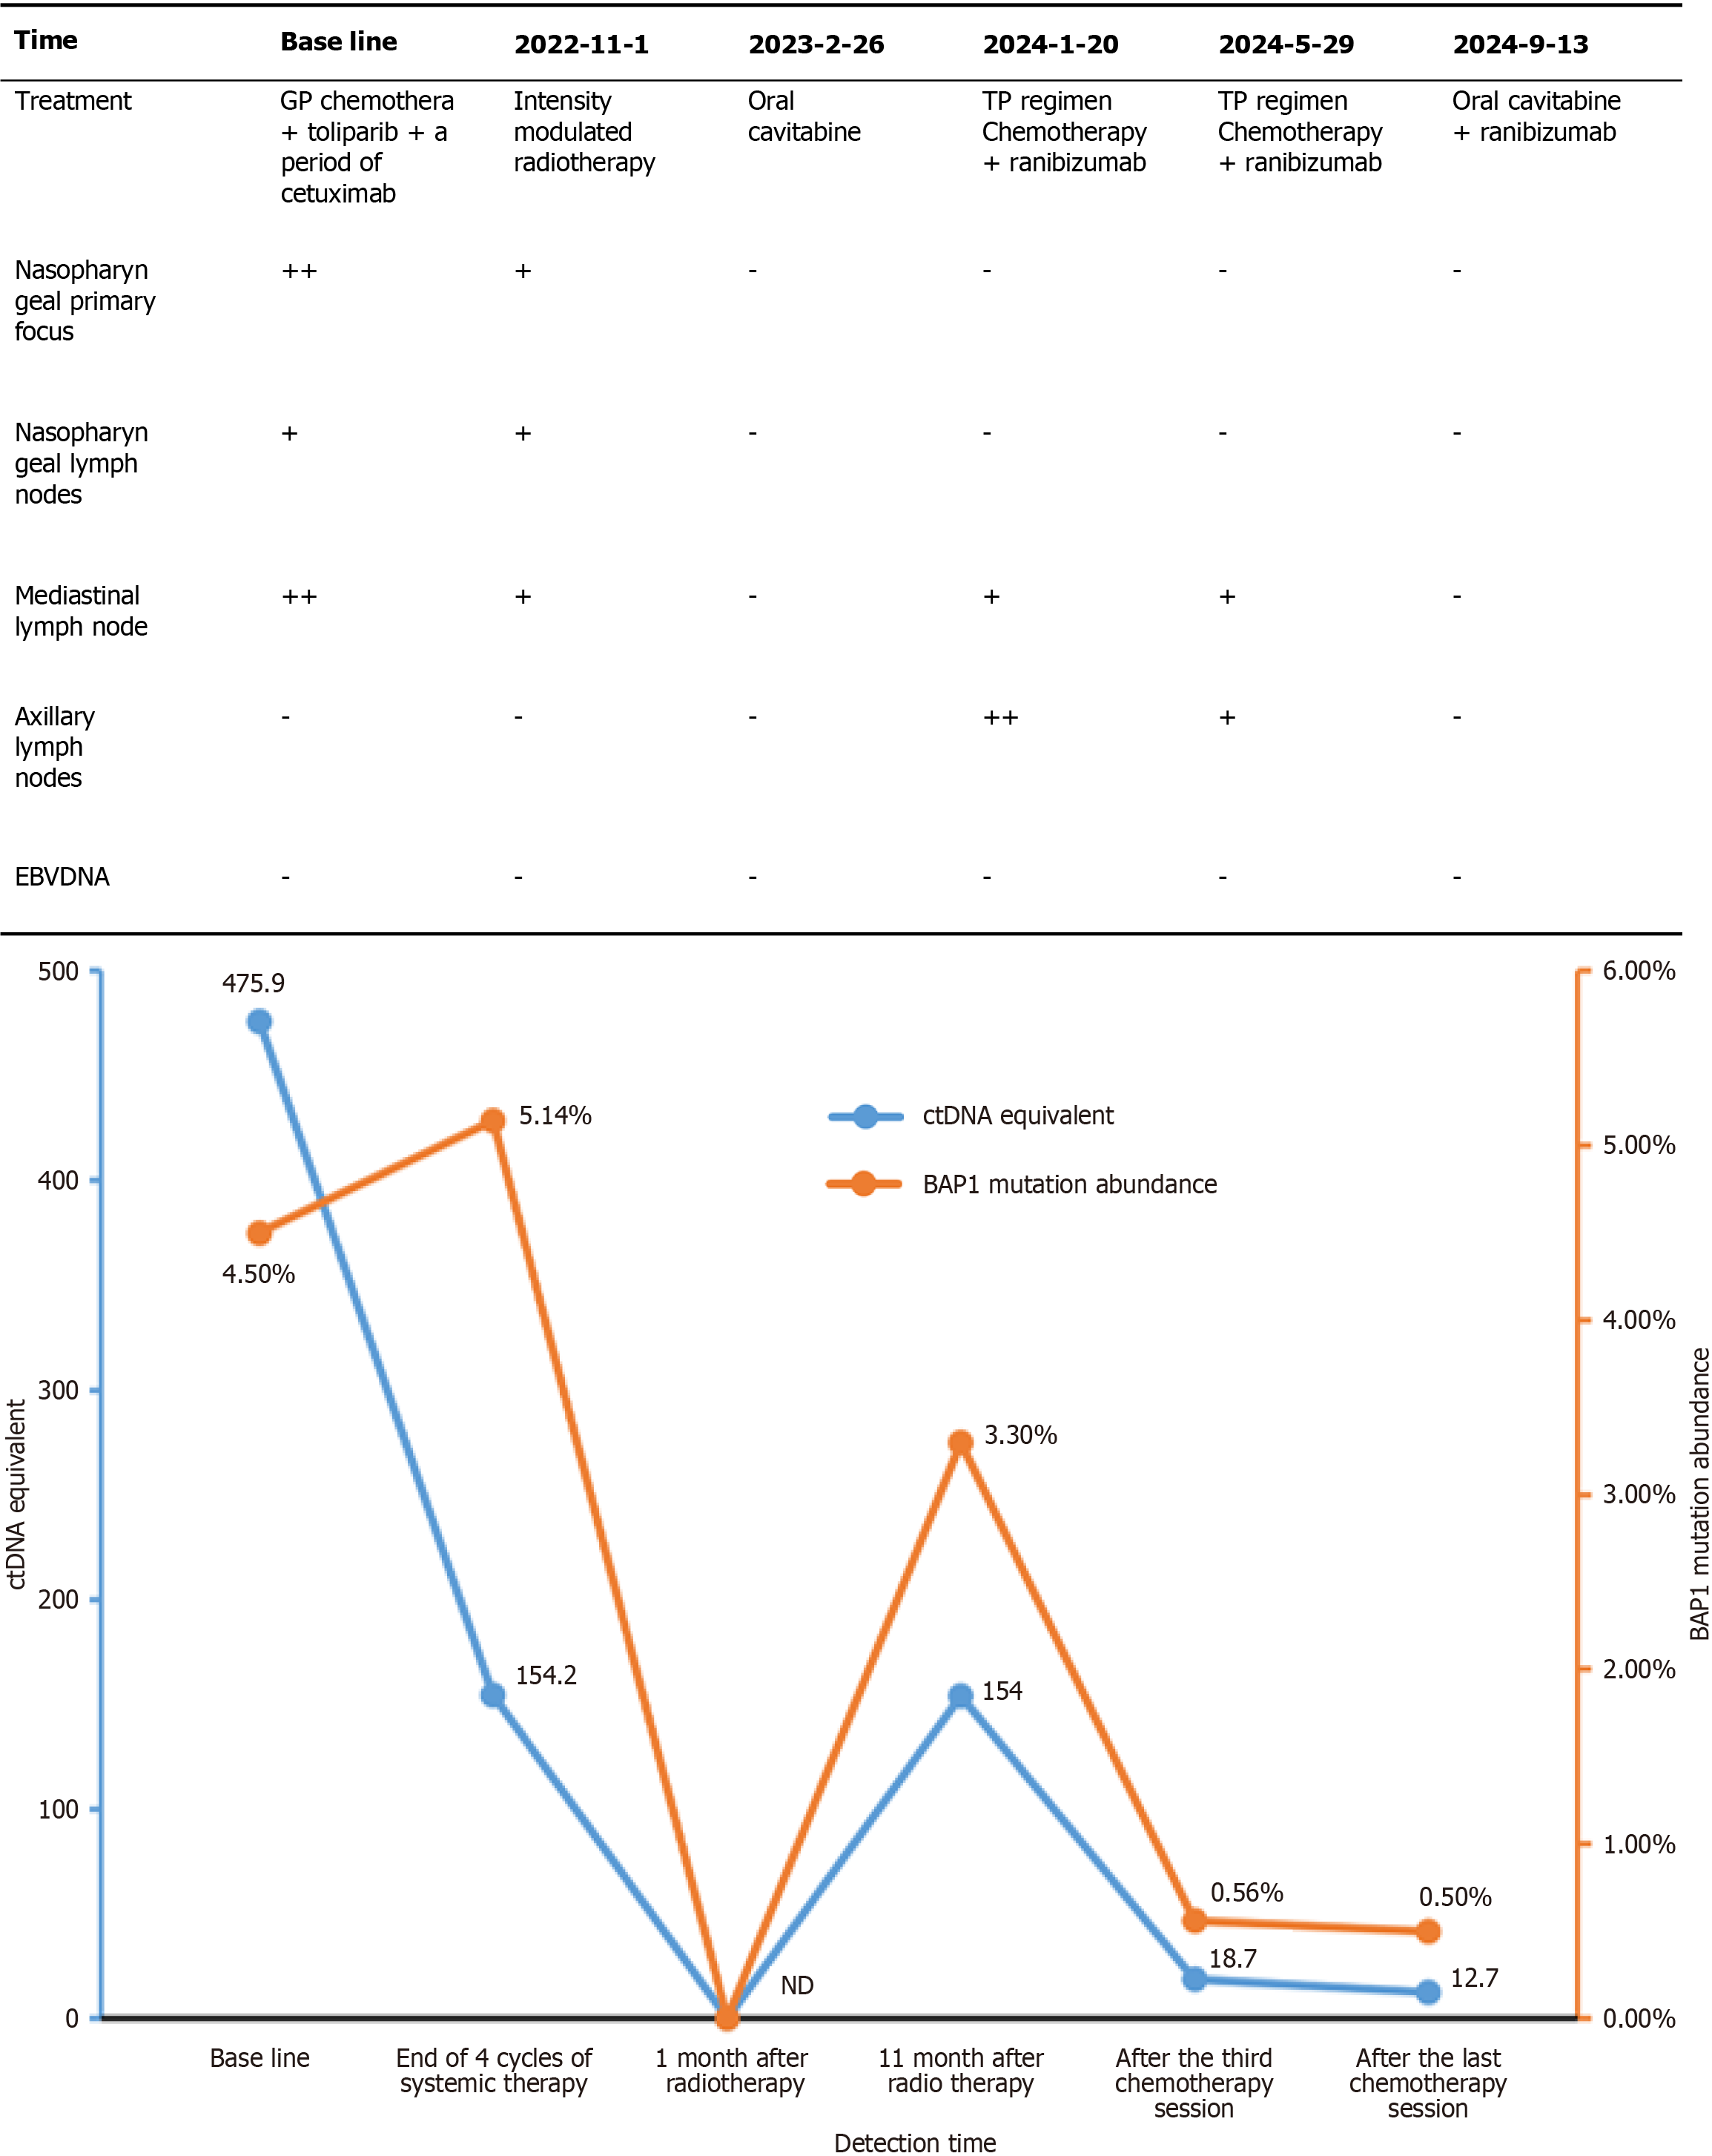

Figure 4 Table of patient's disease progression during treatment and line graph of the abundance of circulating tumor DNA -specific tumor mutations in liquid biopsies as a function of treatment time point.

EBV: Epstein–Barr virus.